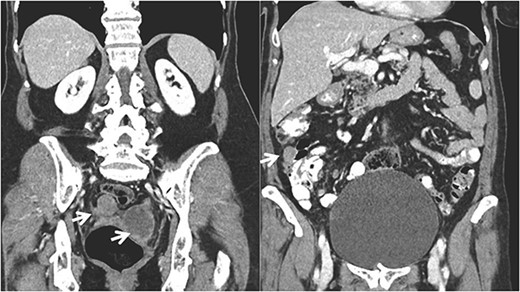

A 68-year-old patient, initially diagnosed with a FIGO stage IIA fallopian tube carcinoma, was under active follow-up in the Gynecologic Oncology Clinic at our institution since 2020. She underwent primary cytoreductive surgery in August 2019 (hysterectomy, bilateral salpingo-oophorectomy, omentectomy, pelvic and para-aortic lymphadenectomy, without any residual macroscopic disease) and completed six cycles of postoperative chemotherapy (carboplatin and paclitaxel) in January 2020. She was free of disease until May 2022 (disease free interval—26 months) when her CA 125 began to rise (52 U/L). CT and MRI scans showed splenic and subcapsular hepatic implants, two metastatic pelvic nodules with 31 and 58 mm next to the sigmoid colon and rectum, and several mesenteric implants in the descendent colon (Figs 1 and 2).

Coronal CT imaging showing the pelvic tumor implants and in the right colon.

Correlation between the 3D model and surgical findings on the right colon and tumor implants (arrows).